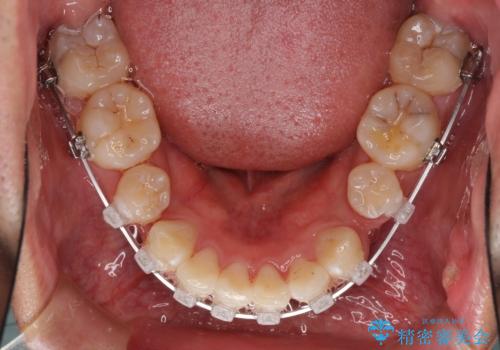

- クリアブラケット

- 3年3ヶ月

- 10-30回

奥歯の咬み合わせを改善したいため、治療期間が長くなりましたが、患者様には辛抱強くお付き合いいただきました。

上下の正中を合わせることもでき、患者様には大変満足していただきました。